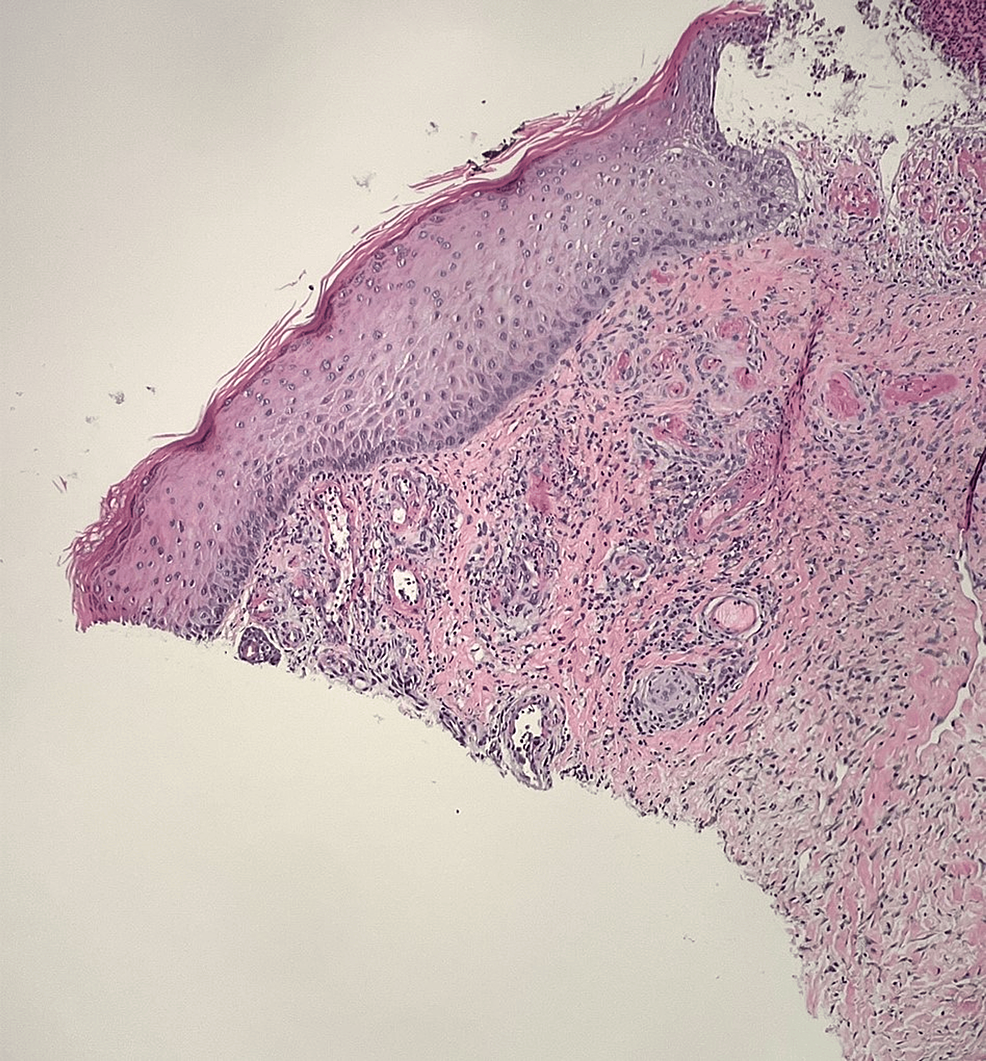

From www.cureus.com

Cureus Livedoid Vasculopathy with Severe Debilitating Neuropathy in a Athletes With Neuropathy Neuropathic pain is not uncommon to encounter in athletes although not always recognised. Now he is an example for his contemporaries confronting diabetes and neuropathy. Jerry mathers embodied an american ideal in leave it to beaver from 1957 to 1963. Neuropathic pain, where a person might feel pain from any part of their body, is nerve pain that occurs after. Athletes With Neuropathy.

Cureus Livedoid Vasculopathy with Severe Debilitating Neuropathy in a Athletes With Neuropathy Neuropathic pain is not uncommon to encounter in athletes although not always recognised. How to know when your pain is actually a symptom of nerve damage. The warriors are officially listing looney as out for an unspecified amount of time as he searches for answers on how best to treat and manage his neuropathy. We tapped 3 experts to explain. Athletes With Neuropathy.

Cureus Livedoid Vasculopathy with Severe Debilitating Neuropathy in a Athletes With Neuropathy How to know when your pain is actually a symptom of nerve damage. Athletes with persistent numbness in the hands and feet may have a peripheral neuropathy or cervical or lumbar stenosis. Logging miles during training can cause significant. The warriors are officially listing looney as out for an unspecified amount of time as he searches for answers on how. Athletes With Neuropathy.

Cureus Livedoid Vasculopathy with Severe Debilitating Neuropathy in a Athletes With Neuropathy Logging miles during training can cause significant. Researchers use several animal models to understand the utility of exercise as a treatment for neuropathic pain by employing different behavioral tests to understand. Jerry mathers embodied an american ideal in leave it to beaver from 1957 to 1963. We tapped 3 experts to explain when it could signal something more serious. Now. Athletes With Neuropathy.